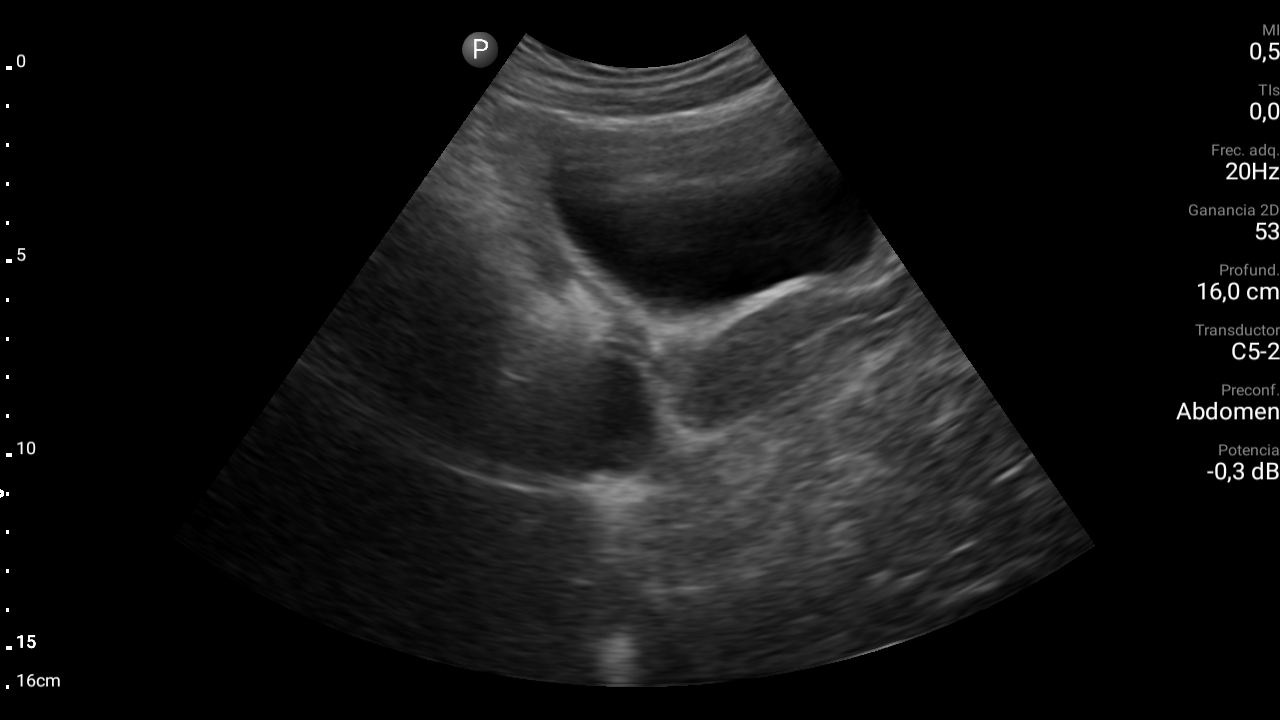

Hallazgos ecográficos

En ecografía abdominal se observa masa hipoecoica dependiente de útero por lo que se remite de forma preferente a ginecología.

En ginecología le realizan ecografía transvaginal, siendo diagnosticada de mioma uterino.